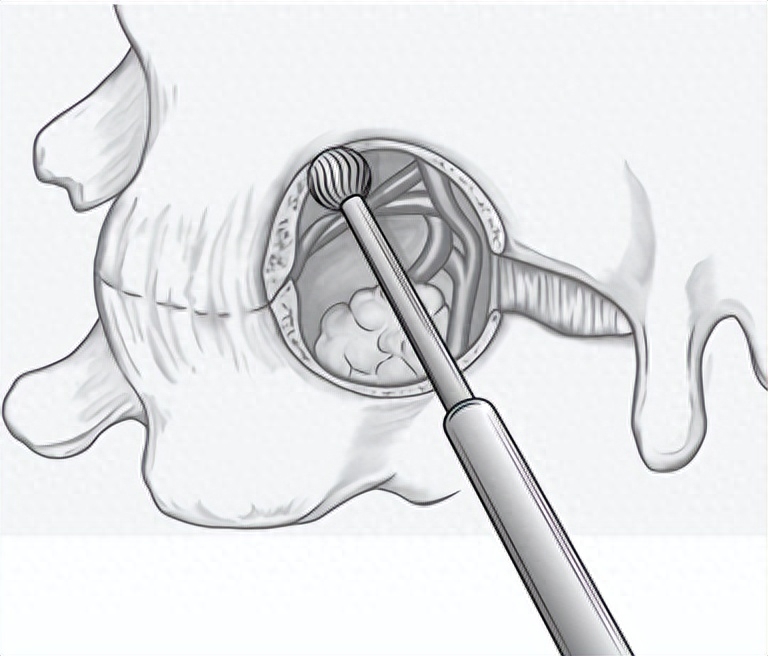

颈椎后路keyhole手术

keyhole手术示意图

颈椎后路keyhole手术,即脊柱内镜下后路颈椎椎间孔切开术,无需经过前方诸多重要组织结构,通过内镜的通道在颈椎后方运用“钥匙孔”技术从椎间孔后“开门”进入,不切除棘突,不破坏椎板和椎间盘之间结构,对颈椎后方韧带复合体损伤较小,降低了软组织剥离等相关并发症的发生率,提高了在敏感的神经结构周围实施手术的安全性。